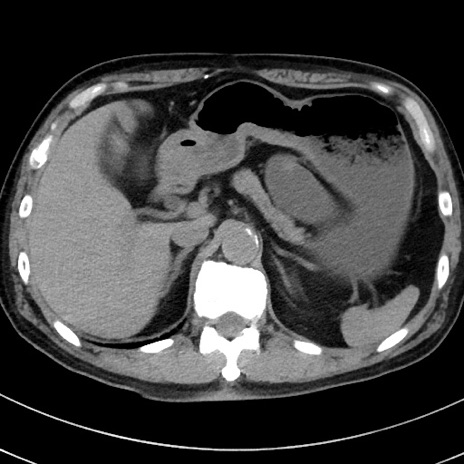

症例38(横断像)

【症例】70歳代 男性

【主訴】腹痛・嘔吐

【現病歴】昨晩より、嘔吐・腹痛あり。今朝になっても嘔吐あり。来院。

【既往歴】心臓バイパス手術、開腹胆摘、腸閉塞

【身体所見】BP 107/71mmHg、HR 116/min、腹部:平坦、軟、下腹部に軽度圧痛あり。反跳痛なし。

【データ】WBC 15100、CRP 0.32